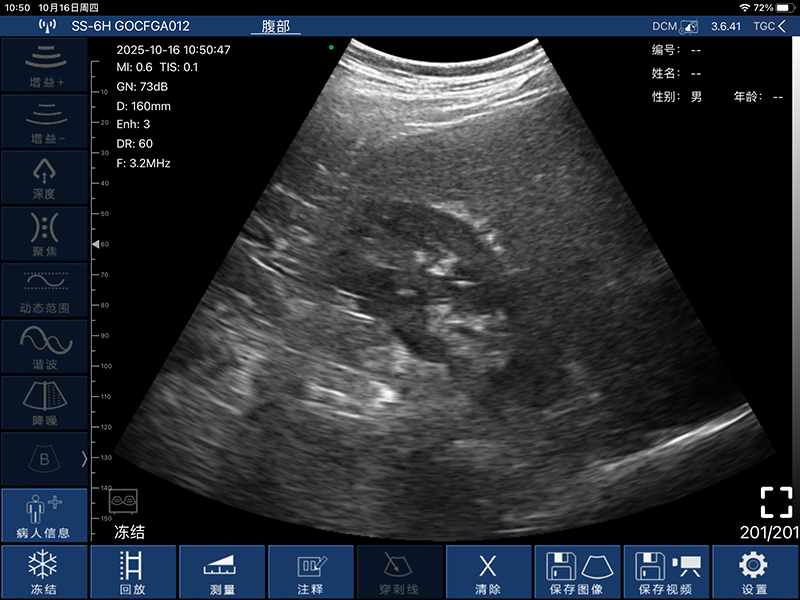

• 扫描方式:电子阵列扫描

• 探头频率:3.2/5.0MHz

• 增益30db-105db

• 扫描深度:90/160/220/305mm,可调

• 显示模式:B、B/M、Color、PW、PDI

• 图像调节:增益、焦点、反相脉冲谐波、降噪

• 电影回放:手动和自动回放,可设置回放帧数为100/200/500/1000